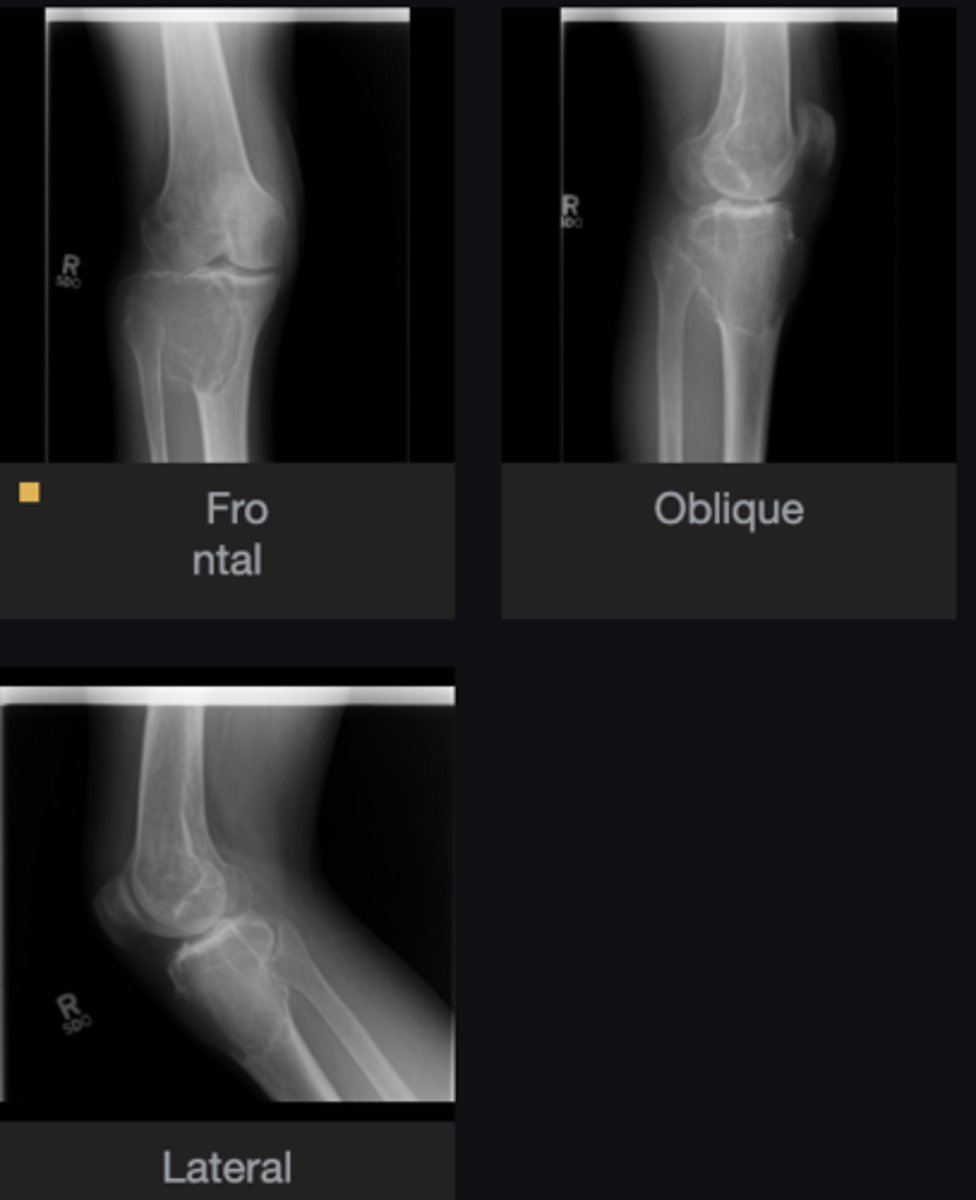

- Solitary

- Eccentric

- Geographic

- Multiloculated

- Fibrous matrix

- Small

- Cortical thinning

- Sclerotic border

Describe the lesion

Non-Ossifying Fibroma

Diagnosis?

- Anterolateral distal tibia

- Metaphysis

- Septation

- Look for fracture

- Refer to orthopedist

Next step?